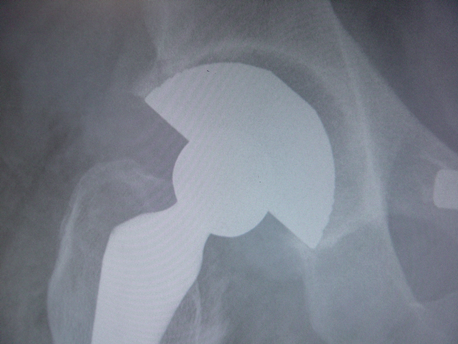

Figure 1 (A): Case one: 6 mm gap in Zone II on postoperative day-1

radiograph in a 67 year old man

Figure 1 (B): Case one: Complete fill-in of gap at three months follow-up

Figure 2 (A): Case two: 3 mm gap in Zone II on postoperative day-1

radiograph in a 62 year old man

Figure 2 (B): Case two: Complete fill-in of gap at three months follow-up